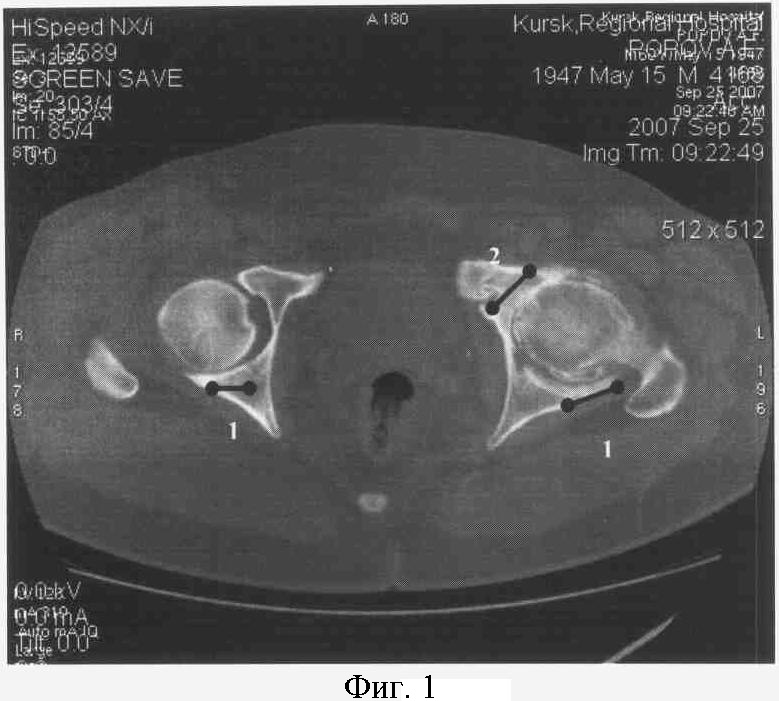

На фиг.1. представлен КТ срез на уровне ямки головки бедра.

Справа: 1-я стадия коксартроза с локализацией ограниченного участка в заднем отделе сустава (1).

Слева: 3-я стадия коксартроза с кистевидной перестройкой с локализацией ограниченного участка в заднем (1) и переднем отделах сустава (2).